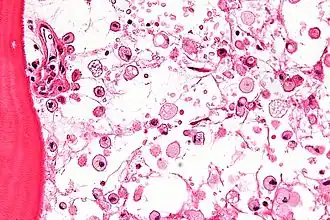

На микрофотографии характерные изменения строения костного мозга при болезни Гоше — цитоплазма макрофагов напоминает смятую папиросную бумагу. Окраска гематоксилином и эозином | |